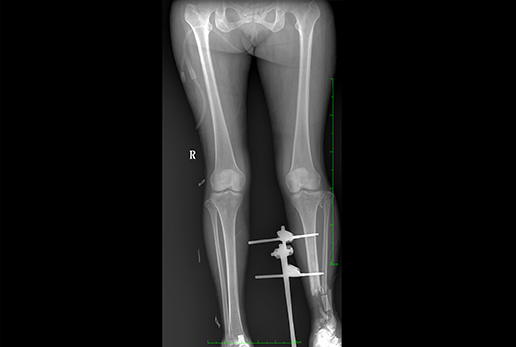

● 核心優(yōu)勢: 大功率 動態(tài)平板 高清攝影 快速成像 透視造影 高清點片

● 采用自主研發(fā)脈沖技術(shù),大尺寸動態(tài)平板,可實現(xiàn)動、靜態(tài)攝影模式無感切換,呈現(xiàn)更優(yōu)質(zhì)的圖像,為臨床醫(yī)生提供診斷依據(jù)。

● 高清點片

在透視檢查下,可進(jìn)行毫秒級高清點片,準(zhǔn)確捕捉病灶,為醫(yī)生提供高清的診斷依據(jù)。